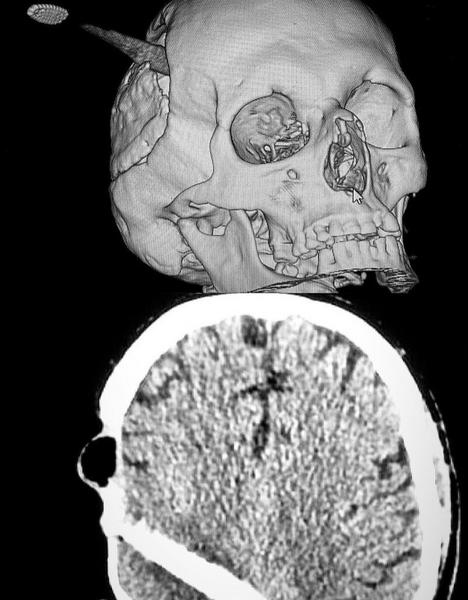

В татарстанской РКБ медики вытащили зубную щетку из головы мужчины, которая вошла в мозг. Находившегося в созании пациента привезли в больницу ночью 21 февраля, сообщили в Инстаграм-аккаунте больницы.

Жителя Казани сразу повезли на КТ, позже выяснилось, что жизненно важные участки не задеты. Но срочно нужна была операция. Пациентом оказался врач из далекого региона. Полтора года назад он получил тяжёлую травму головы, перенёс открытую операцию на головном мозге. Долго восстанавливался и продолжал оперироваться, чтобы восстановить кожу в области травмы.

Как отметили в РКБ, щетка вошли в мозг почти по самую щетину в то место, где была первая травма. Однако мужчине повезло — сглаженные края ручки зубной щётки как бы «раздвинули» мозг.

— Не было обильного кровоизлияния, гематомы и как такового сдавления головного мозга, – подчеркнули в медучреждении.

Хирурги отделения нейрохирургии №2 аккуратно извлекли щетку из головы, предполагая любой исход. Из-за внезапного кроветечения мужчина мог умереть, но пролившаяся 4 часа операция прошла хорошо. Врачи совместно с микрохирургом сделали пластику кожных покровов.

— Через пару дней врача-пациента перевели из реанимации в отделение, и он постепенно пошёл на поправку. Как зубная щетка оказалась в черепе, история умалчивает. Но наш герой однозначно «родился в рубашке», – сообщили в клинике.